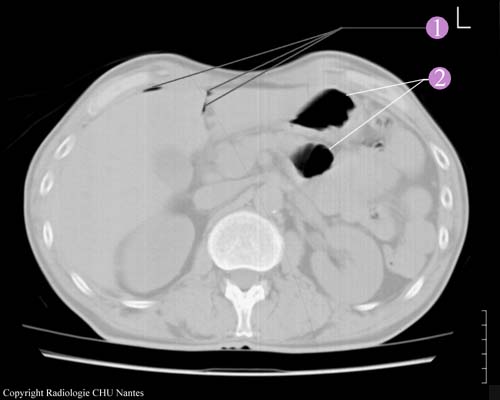

Examen tomodensitométrique

1.Air en avant du foie et dans le sillon du ligament rond.

2. Air dans le colon ( c’est normal ).

Il faut savoir que l’ASP était normal, donc il faut être vigilant.